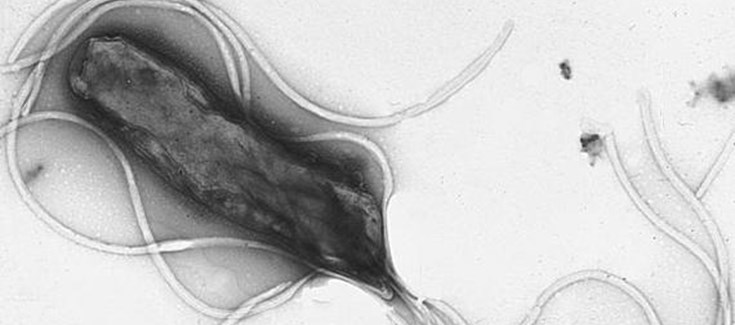

Helicobacter pylori. Foto: Sync